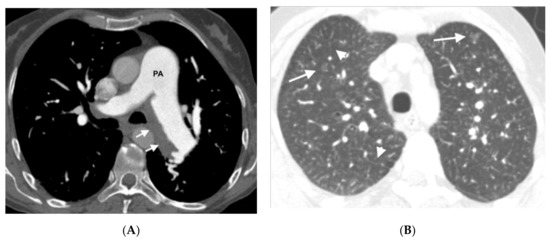

Figure 2.

Forty-six-year-old man referred from another center with a diagnosis of idiopathic PAH. (A) MDCT on admission: parenchymal involvement with faint centrilobular nodules in ground glass (arrows); (B) MDCT after initiation of vasodilator treatment. Radiological worsening with increased ground glass involvement and the appearance of septal lines (arrows) in relation to pulmonary edema. The patient was finally diagnosed with hereditary PVOD.